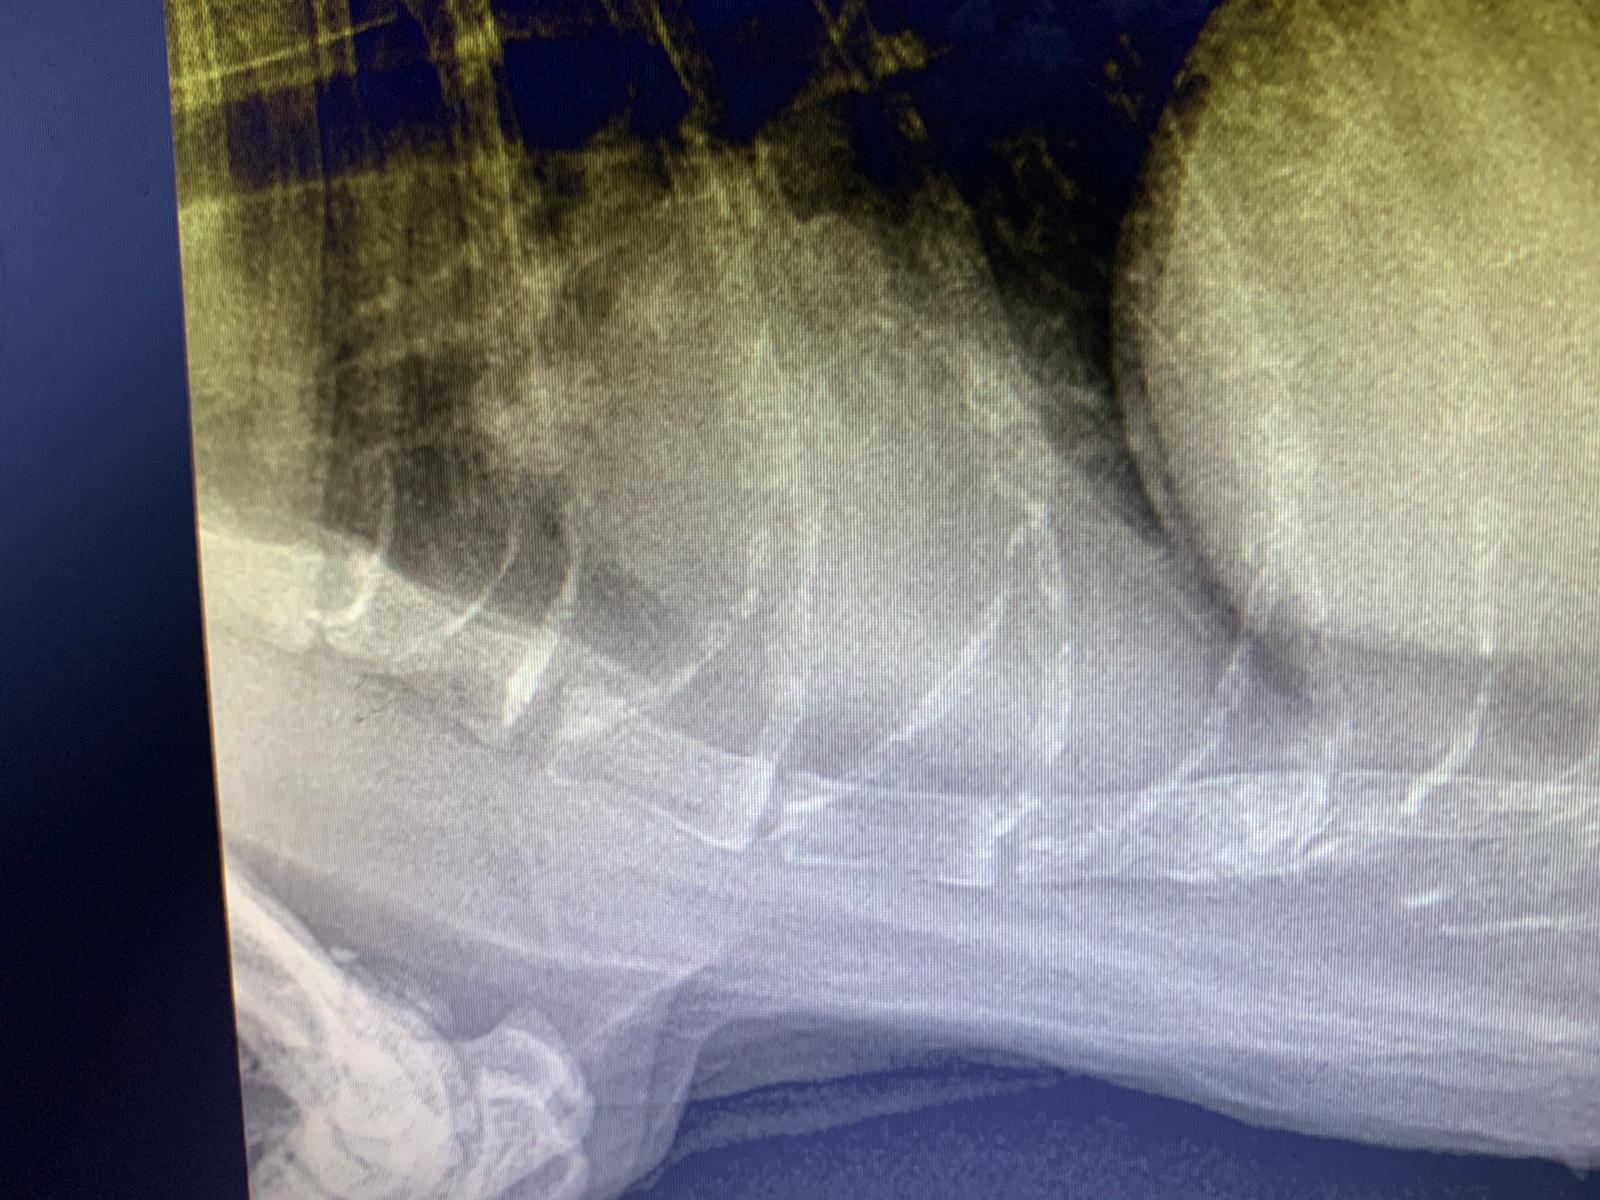

Dr nally says don’t like the muffed sound of his lung, noisy, i scare got fluid ah. Taken X-ray.

X-ray show he got one lump of fluid on the left, cannot confirm what it is. Unless abdominal u/s – I rather spend money on bupre.

His lower spine one part should be in pain.